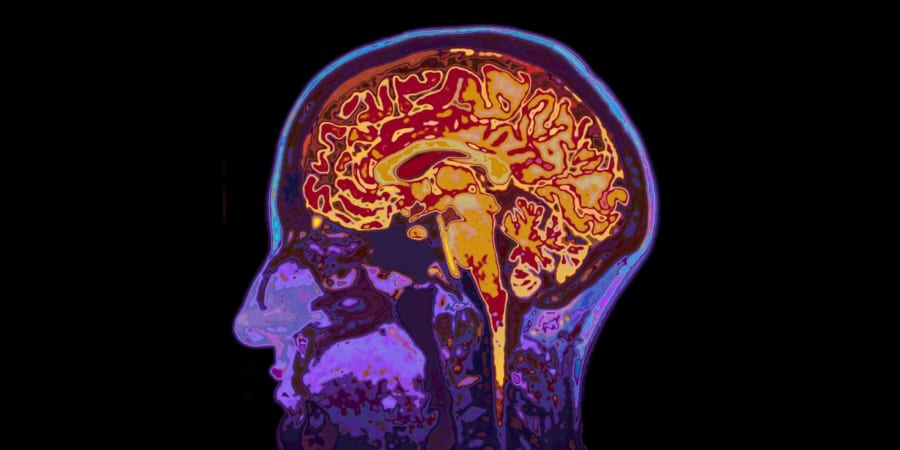

体のどこかにあるがんがシスタチンCというタンパク質をたくさん分泌し、それが血液を流れて脳に入りこみ、TREM2というスイッチを通してミクログリアのゴミ掃除を強めます。

その結果としてアミロイドβのプラークが減り、記憶力もある程度守られる──という流れが、マウスの実験でかなりはっきりと示唆されました。

それに対して、シスタチンCはすでにできてしまったプラークにくっつき、ミクログリアのTREM2を通じて「今あるゴミ山をどう片づけるか」に働きかけます。

研究グループを率いるルー博士らは、「体の外側にできたがんが分泌するシスタチンCが、脳のミクログリアを通じてすでにできてしまったアミロイド斑を分解させる。これは、これまでの“アミロイドがたまらないようにする”戦略とは違う、新しい治療の道を示している」とまとめています。